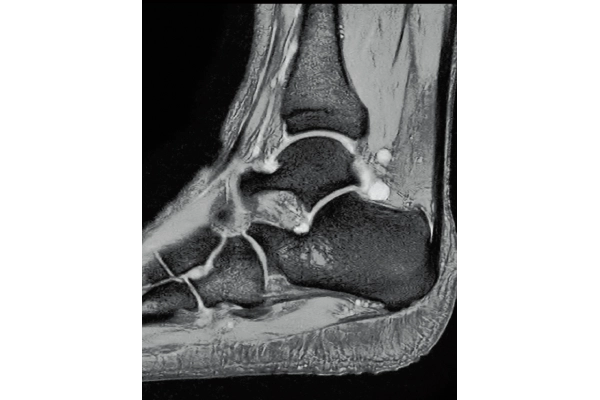

3D Bone

0.93×0.93×1.2(0.6)mm

1.1×1.1×1.2(0.6)mm

Lower extremity

non-contrast MRA (MIP)